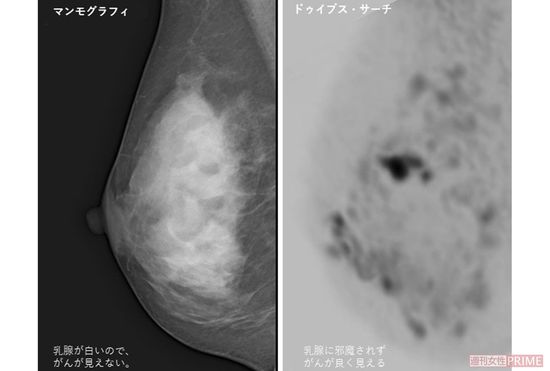

左はマンモグラフィーで撮影した高濃度乳房。白っぽく写りわかりにくいが、右のドゥイブス・サーチでは腫瘍がよく見える※画像提供・高原医師

[写真 2/2枚目] 左はマンモグラフィーで撮影した高濃度乳房。白っぽく写りわかりにくいが、右のドゥイブス・サーチでは腫瘍がよく見える※画像提供・高原医師